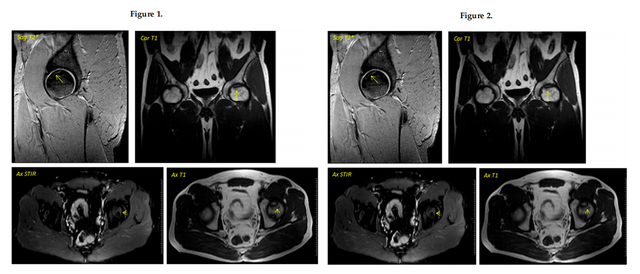

④影像学变化:在早期阶段变化并不明显,第6个月开始所有患者出现改变;62.5%的患者(n = 5)在手术后的一年内实现了影像学稳定(部分患者影像学图1、2)。